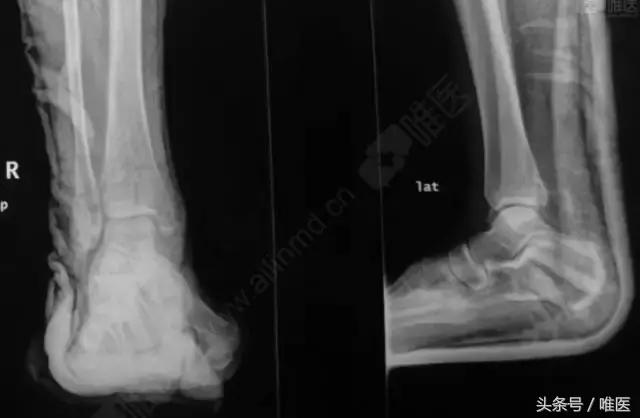

X线:右侧踝关节骨折

CT二维重建: 右侧踝关节骨折

治疗前影像